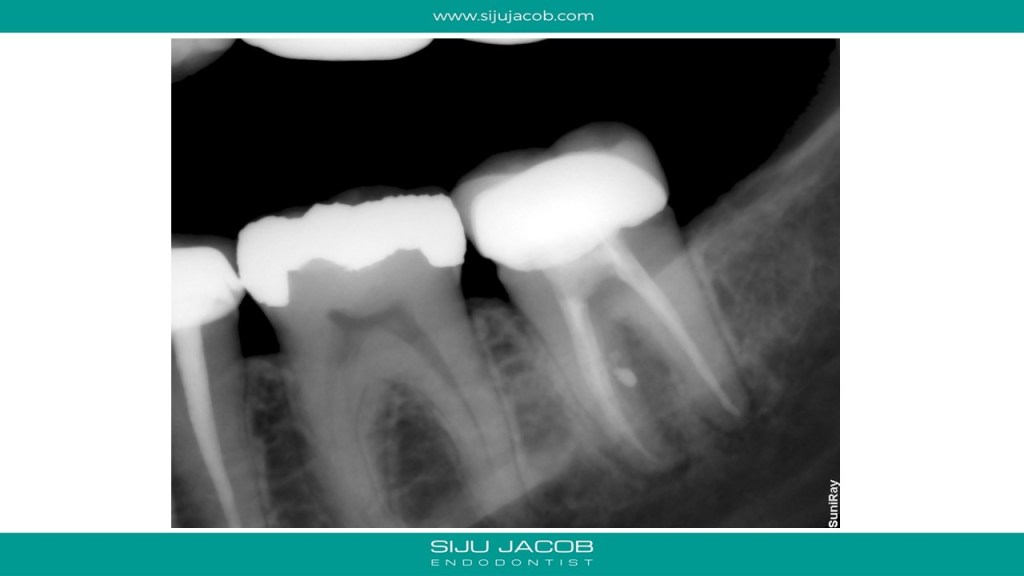

This patient had pain on a previously endo treated and crowned mandibular second molar. CBCT showed a missed mesio-lingual canal. I decided to Re-treat the Mesio-buccal canal as well because the CBCT scan showed that the missed mesio-lingual canal merged with the mesio-buccal canal apically.